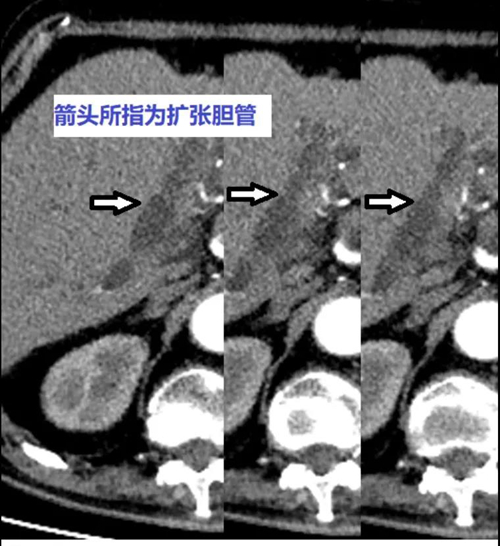

現(xiàn)年85歲的吳老太(化名)患有高血壓、心臟病、冠心病等多種疾病,身體狀況一直不好。近來她出現(xiàn)腹部持續(xù)性疼痛、嘔吐等癥狀,被家人緊急送往北京大學(xué)人民醫(yī)院青島醫(yī)院(青島婦兒醫(yī)院城陽院區(qū))急診救治。經(jīng)過檢查,吳老太被診斷患有膽總管結(jié)石伴梗阻性化膿性膽管炎,需要轉(zhuǎn)入肝膽外科病房治療,后續(xù)通過手術(shù)取出結(jié)石。

入院后,吳老太淤積的膽汁在膽管內(nèi)繼發(fā)感染,一天內(nèi)數(shù)次高燒、寒戰(zhàn),血壓降至80/50mmHg以下,甚至出現(xiàn)多器官衰竭。因為老人病情危重,無法耐受常規(guī)手術(shù)創(chuàng)傷,如何以損傷最小、風(fēng)險最低的治療方案疏通膽道梗阻成為目前的燃眉之急。